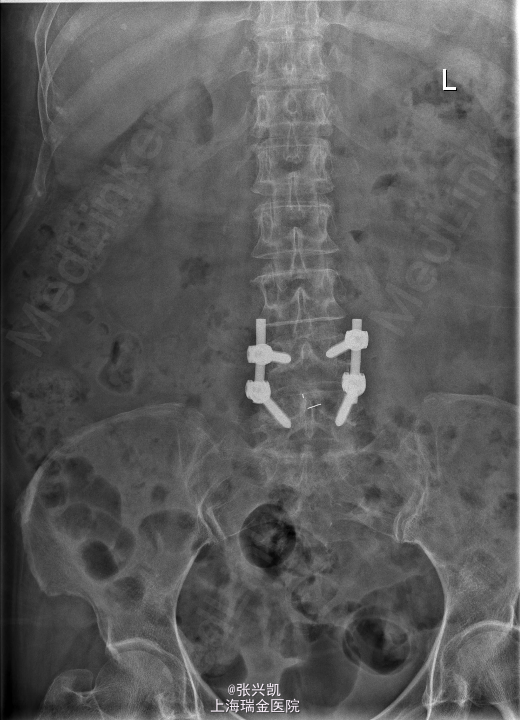

诊断:腰椎椎管狭窄L4-5 L4椎体滑脱 处理:腰椎后路减压复位融合内定术

随访:患者术后三月随访,下肢疼痛症状消失,可正常行走,腰部偶感酸胀感 讨论:针对术后有的患者有腰部酸胀不适感,有什么好的对症处理办法?